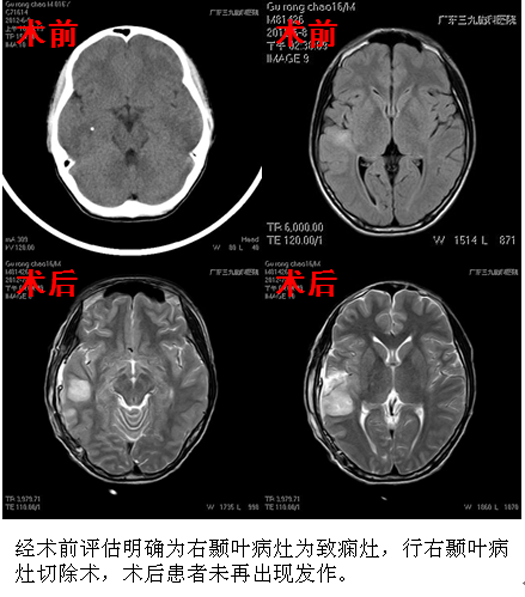

【典型案例:手术治疗】

患者,男性,16岁,病史11年;

患者自5岁开始先出现幻听,有一种奇怪的声音,继之意识不清、头眼歪向左侧,四肢强直抽搐,每次1分钟左右,服用多种抗癫痫药物无效,发作逐渐频繁,入院前每天发作数次。

查体:面部血管纤维瘤、躯干多发色素脱失斑及鲨革斑。